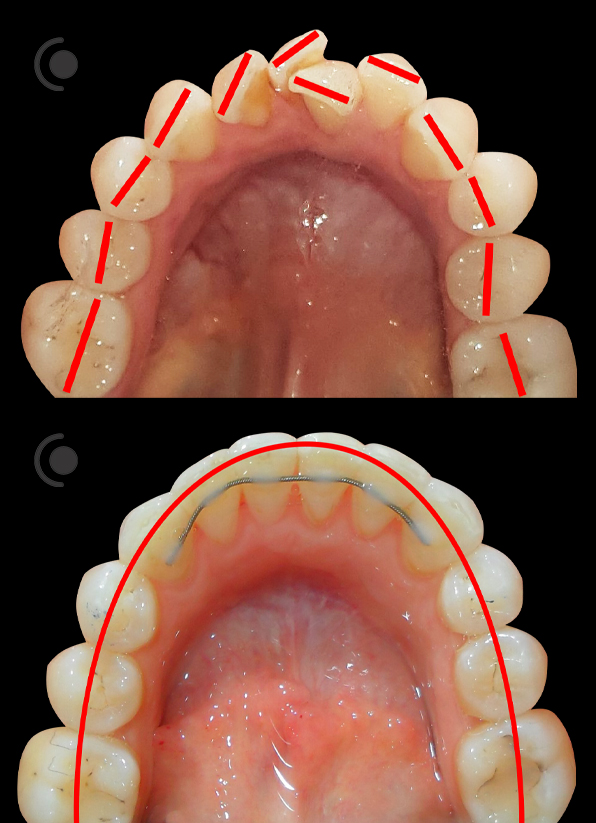

O našoj kvaliteti najbolje govore naši rezultati!

Centar za ortodonciju Petra Džapo